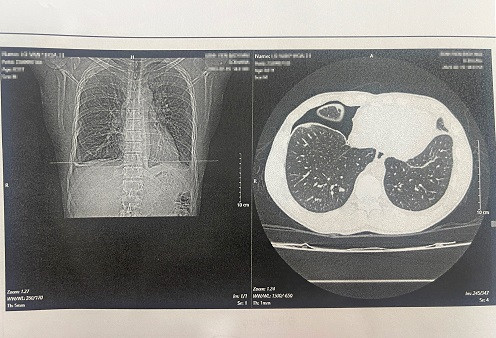

Mới đây, Trung tâm Nhiệt đới Bệnh viện Bạch Mai tiếp nhận một bệnh nhân nam, 31 tuổi, người dân tộc Thái ở Điện Biên nhập viện trong tình trạng tràn dịch/tràn khí màng phổi. Sau khi làm các xét nghiệm cho thấy bệnh nhân dương tính với loại Paragonimus (Sán lá phổi).

Bệnh nhân có đi khám nhưng không tìm ra bệnh. Khi được chuyển đến Trung tâm Bệnh nhiệt đới - Bệnh viện Bạch Mai, với kinh nghiệm nghề nghiệp, các bác sĩ đã cho chỉ định tìm sán và kết quả đúng như dự đoán, bệnh nhân dương tính với loại Paragonimus (Sán lá phổi). Bệnh nhân đã được điều trị bằng thuốc tẩy sán và chỉ sau vài ngày nằm viện bệnh nhân đã được xuất viện.

Hình ảnh phim chụp trên bệnh nhân sán lá phổiHình ảnh phim chụp trên bệnh nhân sán lá phổi

BS Cường nhấn mạnh: Vì ho ra máu, ho tức ngực nên rất nhiều chẩn đoán nhầm sang các loại bệnh khác như lao, viêm phổi, hay u phổi.